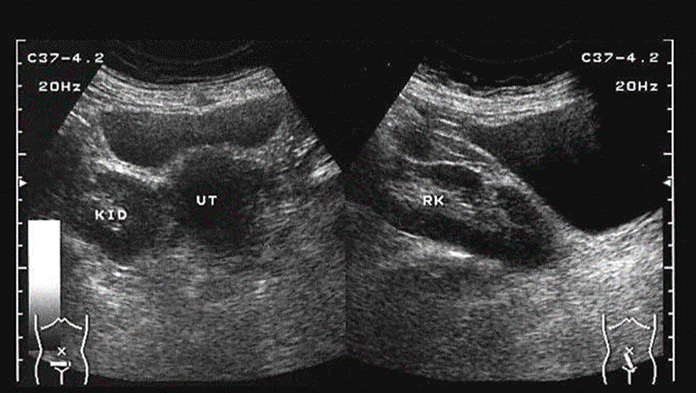

Fluid in Morison’s pouch is seen anterior to the right kidney in this sagittal view. Arrows, Fluid; L, liver; RK, right kidney. **Ascites**